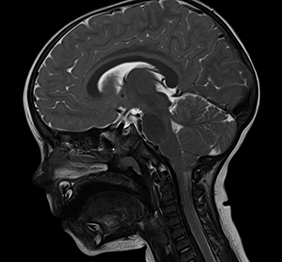

RMN cu sedare la copii

Pentru a obtine un rezultat cat mai exact, protocoalele medicale din domeniul imagisticii recomanda sedarea obligatorie in cazul copiilor sub 3 ani.